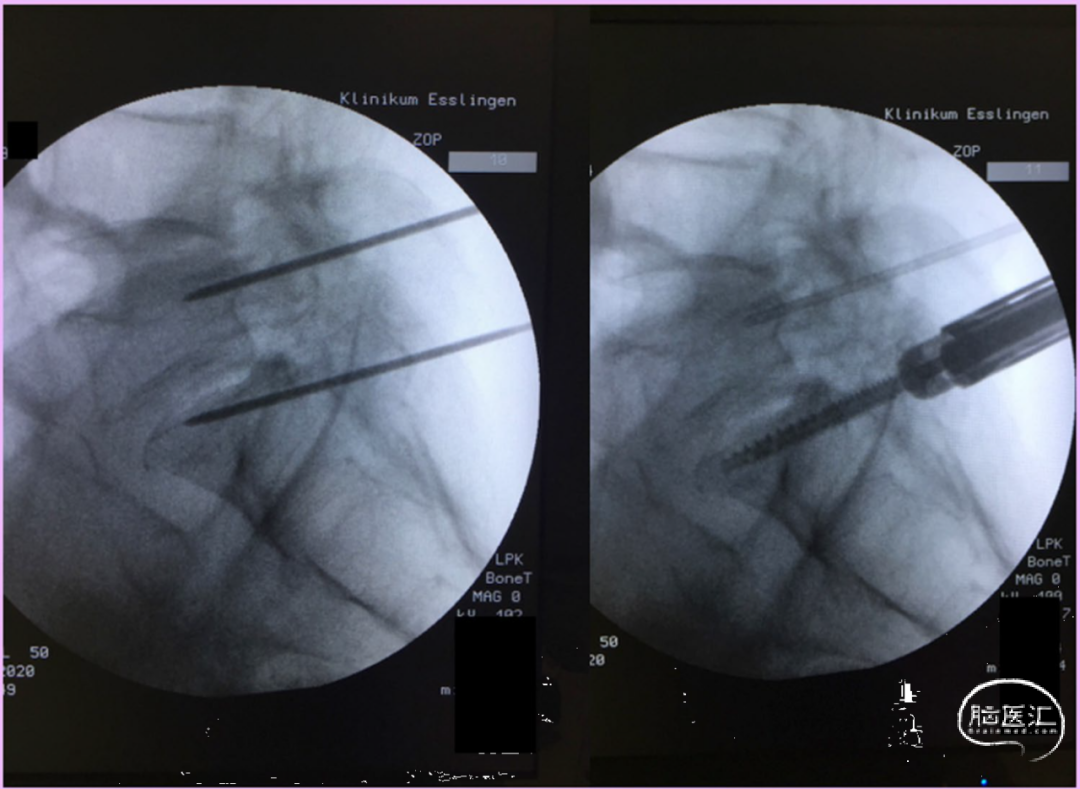

侧卧位旋转手术台10-30°(而不是C臂转动)也可在隧道视图指示下放置椎弓根螺钉(图3、4、5、6)。

图6. 腰骶交界处的侧位视图,控制穿刺针的最终深度,并在导针指引下放置螺钉。